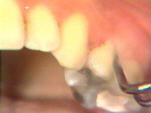

| Aquí puede verse la

permanencia de cálculo al separar con aire el tejido gingival. Este cálculo está

muy alejado para ser eliminado por un instrumento ultrasónico o un instrumento de

mano. Los estudios han mostrado que es prácticamente imposible quitar todo el cálculo

subgingival. A pesar de esto en la mayoría de los casos los tejidos sanan

satisfactoriamente con un tratamiento subgingival cuidadoso. |

En esta región de

la mandíbula también hay cálculo remanente. El principal criterio

es encontrar placa y cálculo remanente cuando hay signos de patología

gingival. Deben retirarse de esos sitios. |

Aquí la condición

gingival en lingual es saludable después de un par de semanas del

tratamiento. |